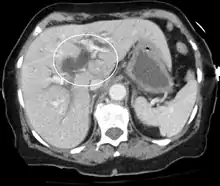

Biliary-tract dilation due to obstruction as seen on CT scan (axial plane)

Most people presenting with jaundice have various predictable patterns of liver panel abnormalities, though significant variation does exist. The typical liver panel includes blood levels of enzymes found primarily from the liver, such as the aminotransferases (ALT, AST), and alkaline phosphatase (ALP); bilirubin (which causes the jaundice); and protein levels, specifically, total protein and albumin. Other primary lab tests for liver function include gamma glutamyl transpeptidase (GGT) and prothrombin time (PT).[28] No single test can differentiate between various classifications of jaundice. A combination of liver function tests and other physical examination findings is essential to arrive at a diagnosis.[29]

Medical imaging such as ultrasound, CT scan, and HIDA scan are useful for detecting bile-duct blockage.[32]